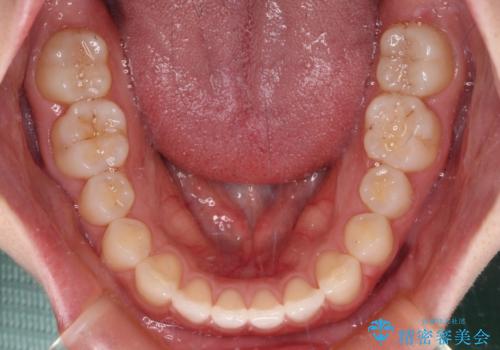

すきっ歯とオープンバイト インビザライン・ライトで改善

- 食いしばりによる顎の負担を気にして来院された患者様です。

当初は、ボツリヌス毒素による咬筋の過緊張の緩和と、睡眠時のマウスピース装着による咬合負担の解消を行いました。

オープンバイトのため、奥歯に負担のかかる咬合状態であったので、矯正治療を提案したところ、希望をされました。

すきっ歯程度の軽度の歯列不正であったため、インビザライン・ライトにより咬合改善を行うこととしました。

オープンバイトやすきっ歯は、舌突出癖によりあっという間に後戻りをするため、矯正治療前からトレーニングを行っていただき、更には後戻り防止のワイヤーリテーナーを併用しています。